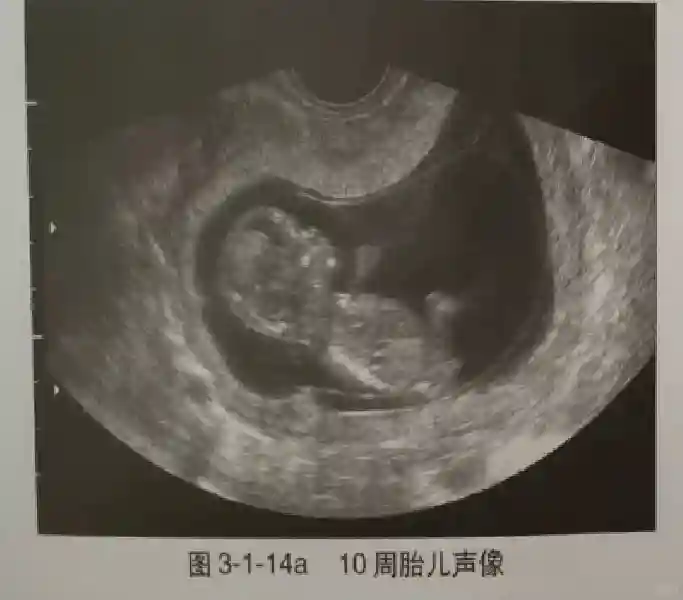

3️⃣胚胎:胚胎通常在6-7周时可以为超声显示,起初为胎芽,表现为卵黄囊一侧局部组织增厚,达到1 -2 mm 时才有可能为超声测量出来。达4-5mm时可见胎心搏动,相应孕周为6-6.5周,妊娠囊大小为13-18mm。胚芽长度≥7㎜时仍未见心管搏动,提示胚胎停止发育。胚胎的出现和妊娠囊直径的关系:妊娠囊直径> 16 mm 时,经阴道超声应显示胚胎。妊娠囊直径> 25 mm 时,经腹超声均应显示胚胎。

4️⃣胎心搏动:胎心搏动通常出现于6-6.5周,胚胎在4- 5mm就应该显示胎心搏动。

5️⃣羊膜:早孕期羊膜囊菲薄,超声常不能显示。孕7周以后加大增益或者用高频超声可以显示羊膜。羊膜囊位于绒毛膜内,胚胎位于羊膜囊内。随着胚胎增长,羊水增多,羊膜囊增大,孕12-16周时,羊膜与绒毛膜全部融合,胚外体腔消失。宫腔线一侧内膜内一圆形增强回声区,中央有小囊状液性暗区,宫腔线局部突起变形,称蜕膜内征,用于判断早早孕。#超声 #早孕检查 #妊娠